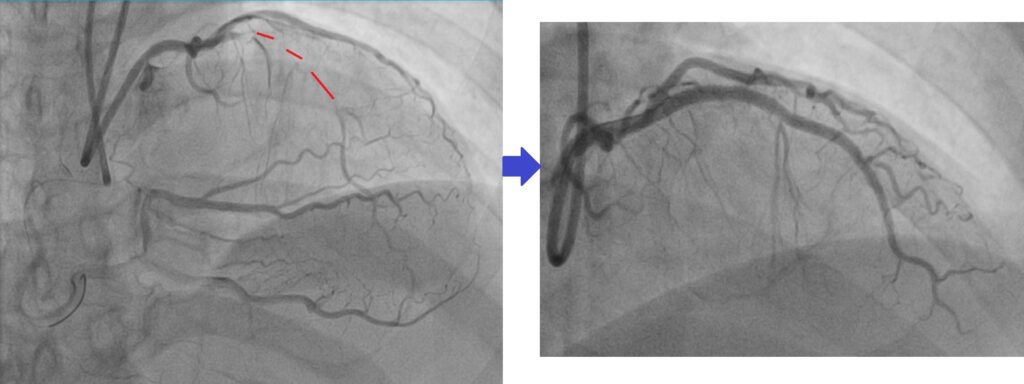

随着技术进步,现在许多 CTO 也可以通过心脏血管介入治疗来打开血管。

在 CTO PCI 手术中,医生会:

- 从手腕或腹股沟血管放入导管

- 使用特殊导丝穿过堵塞的血管

- 用气球扩张血管

- 放置支架保持血管畅通

在经验丰富的中心,CTO PCI 的成功率可以达到 85–90% 以上。